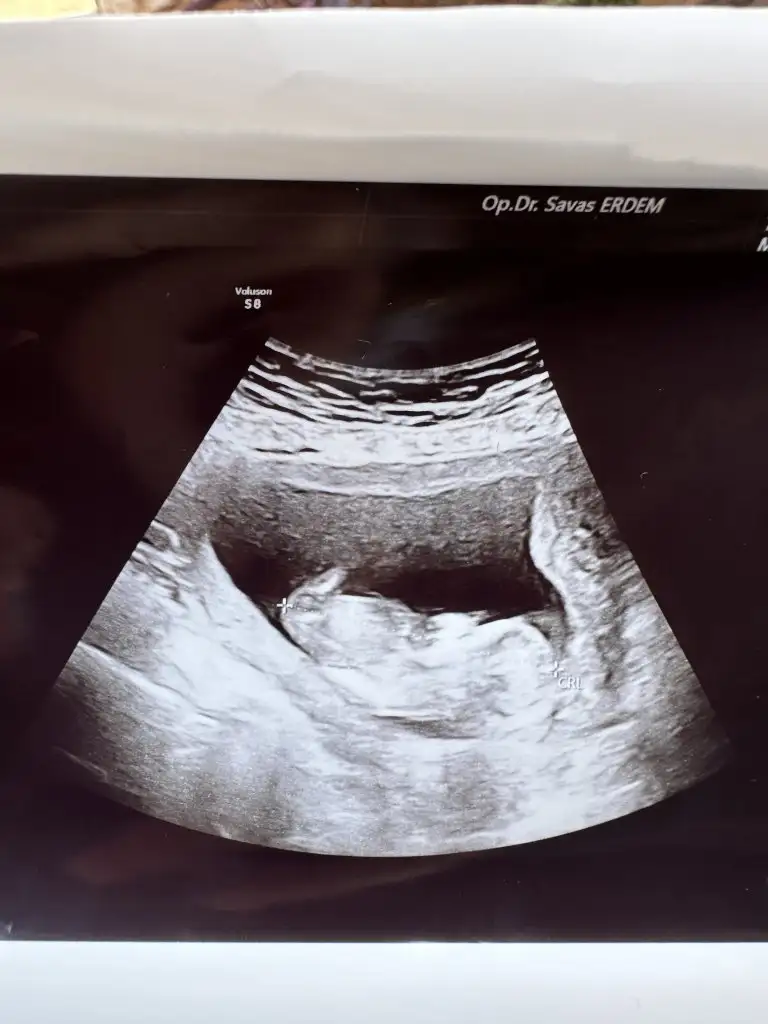

Kız bence. Ama tabiki her şeyin hayırlısı olsun. Şimdi koz diye kodlama. İllaki öğreneceksin.Burda 14 hafta 6gunluk du 92.2m ölçtü yer